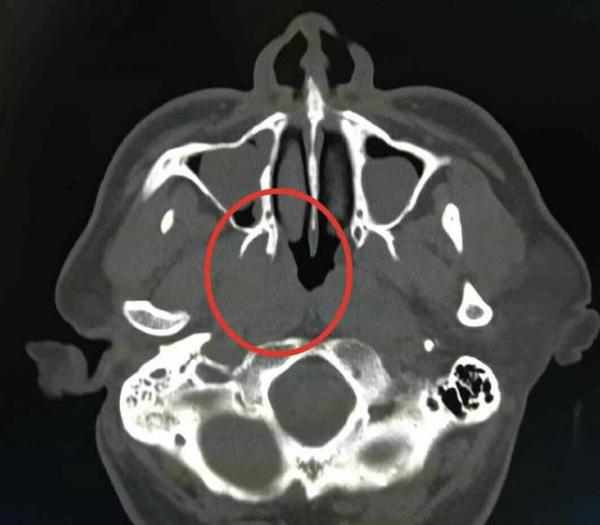

图为常见的头颈部CT影像,由从黑到白的不同灰度的象素构成

以基于灰度的方法为例,王振松说,“计算机可以帮助医生区分CT影像中人眼无法识别的细微灰度变化,但头颈部的软组织在CT图像上的灰度分辨率很低,即便是计算机也很难精准区分,误差较大。而且,如果遇到金属植入物干扰,比如金属假牙在CT成像中会产生一块伪影,导致靶区勾画更加困难。”